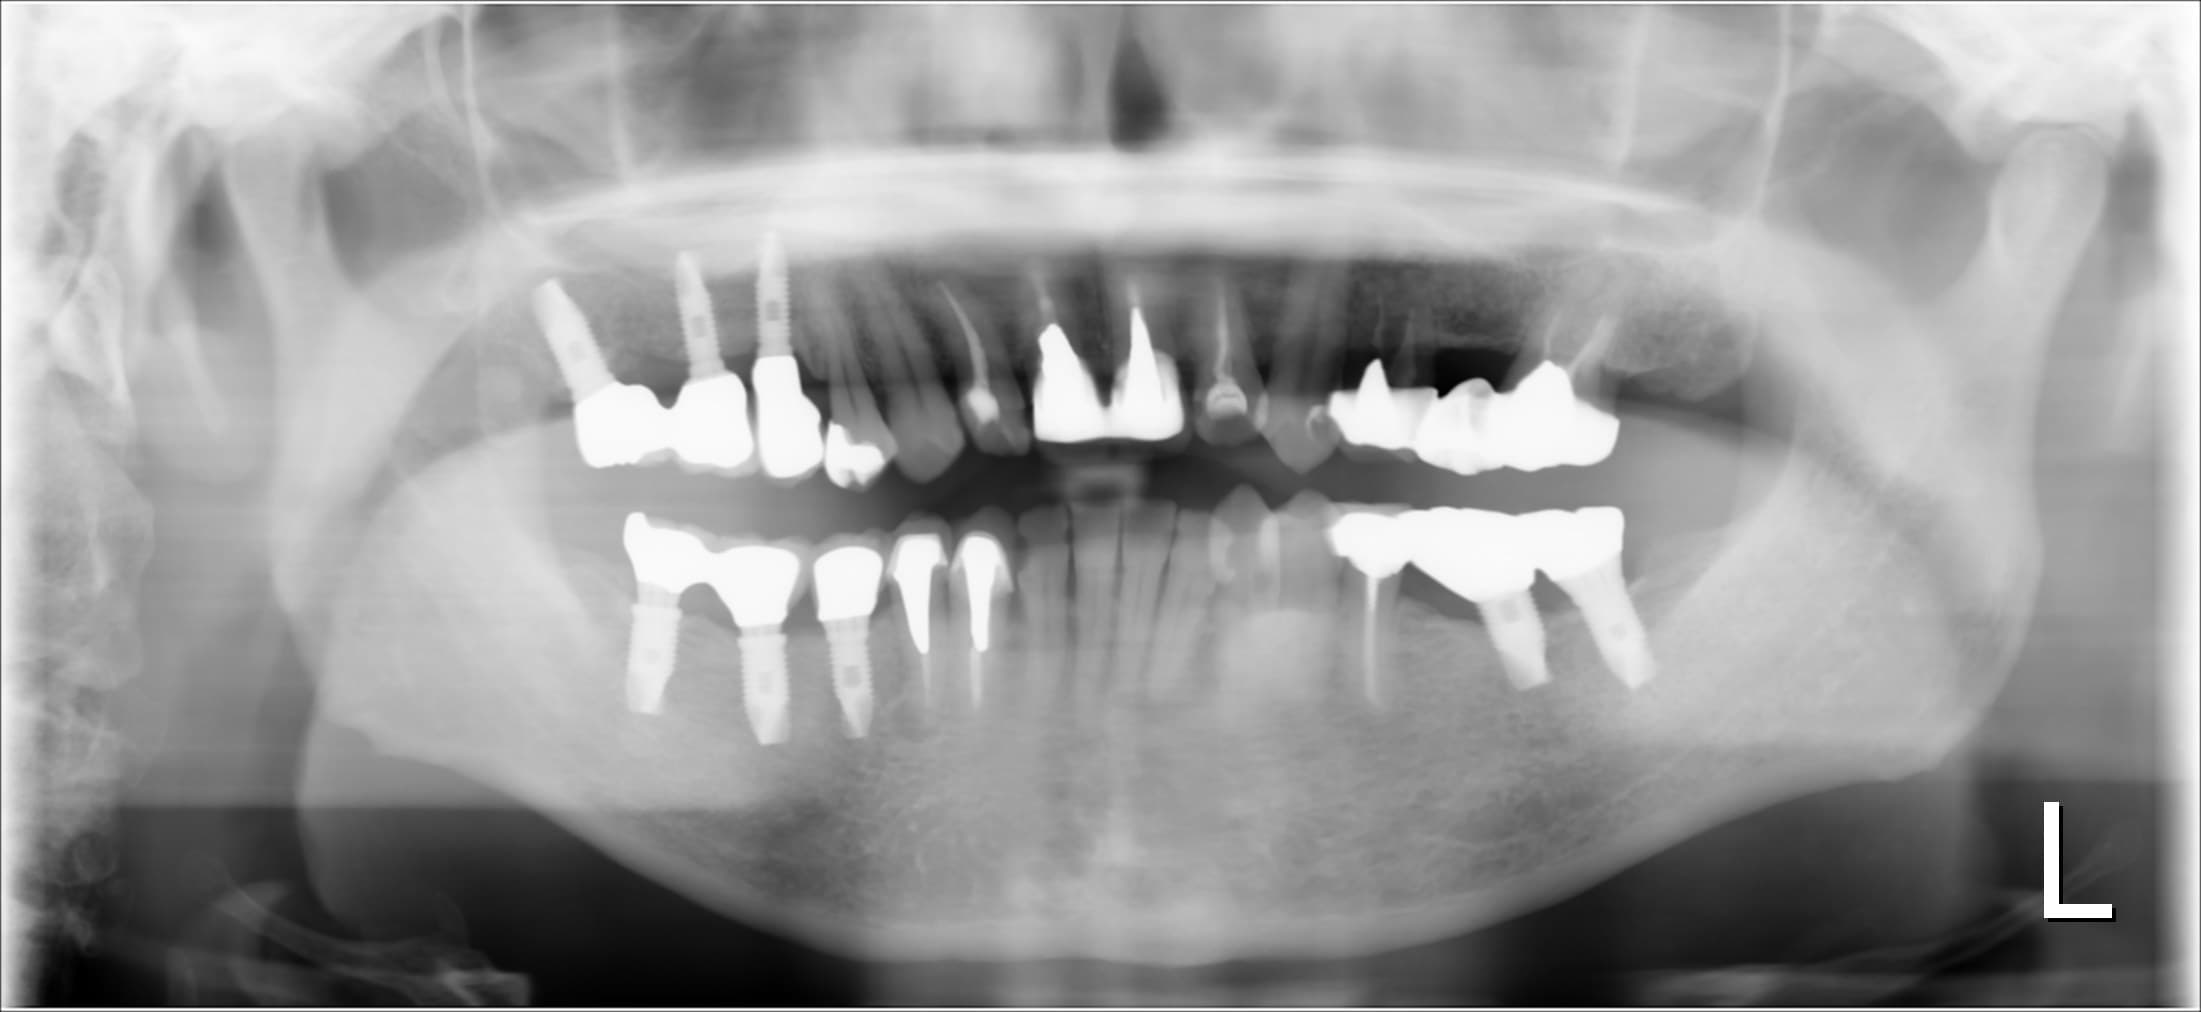

歯周病専門治療 50代男性

こんにちは。 南館歯科クリニックの歯科衛生士の山崎です。 今回ご紹介する歯周専門治療のケースは、50代男性の方です。 30代の頃に虫歯や歯周病の治療を行って以来の歯科医院受診であるそうで…

歯周病専門治療

こんにちは。 南館歯科クリニックの歯科衛生士の山崎です。 今回ご紹介する歯周専門治療のケースは、50代女性の方です。 前歯部の治療を目的として来院されました。 (初診時のレントゲン) 奥…